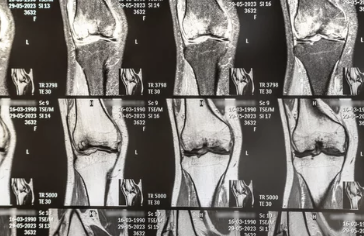

무릎 연골 손상을 의심한다면 전문의 진료를 받아 정확한 진단을 받는 것이 중요합니다. 진단에는 다음과 같은 방법들이 사용됩니다.

- X-ray: 뼈 손상 여부를 확인

- MRI: 연골 상태를 정확하게 진단

- CT: 뼈와 연골 상태를 자세하게 확인